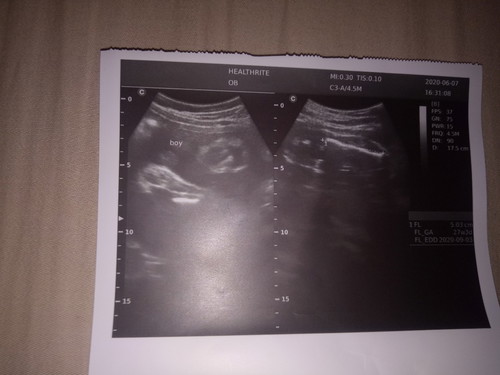

My ultrasound

Nagpaultrasound po ako kahapon medjo nahirapan din po makita yung gender ng baby ko kasi nakaharang daw po yung hita pinaikot ikot po ako ng nag utz sakin para gumalaw si baby .Nung nakita po baby boy daw po kaso nung tinuturo na sakin yung itlog daw po ng baby ko di ko makita kasi malabo yung monitor ?alin po ba jan yung sinasabi na itlog ng baby ko ?